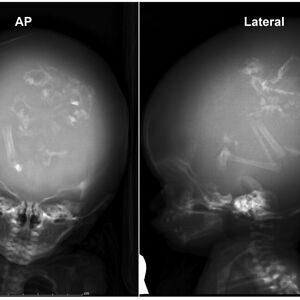

Edit: I have learned more horrible facts about the leopard seal, a creature I now worship out of fear there may be one under my bed. These snake-headed murder puppies are (on average) 10-foot-long 600-pound prehistoric killing machines that see any warm-blooded animal smaller than them as prey. Females have been measured to top 11.5 feet long and weighed at over 1,100 pounds of pure, flesh-ripping terror. The corners of their extremely long mouths are permanently curved upward and sometimes they smile. Shocking no one: this is usually a sign of aggression. Nothing can erase from my mind the image of these terrible fuzzy Jeff the Killer beasts *smiling.* Their heads average 14.5 inches long (awful), with jaws that can open to 160 degrees — significantly larger and any one human limb or head (I hate this). Their teeth? Guys? Holy f**k, their teeth? (TW: slightly gross uncleaned skull)

Their lower jaw is MASSIVE, even for a predator. Leopard seal skulls and bear skulls are too similar for my liking. Seal eyes have spherical lenses (what the f**k), giving them a field of vision of about 280 degrees. With both eyes, they can see basically clearly 360 degrees. Humans have about 130 degrees of visual field, and maybe 180 total degrees of vision. If you can see a leopard seal, it has already seen you. You can’t sneak up on these (need I remind you, virtually silent when hunting) murder monsters. They’re skilled at adapting to many climates and food sources, so much so that in a world where polar bears and orcas are struggling, leopard seals are considered “of least concern” on the endangered species scale. The way they eat penguins is to essentially catch them and throw them into the air until the penguin is fully degloved. They throw penguins *out of their skin*. They also have highly developed craniofacial musculature, allowing them tongue dexterity and a powerful bite force. They sometimes hunt by just… sucking prey into their mouths underwater.

Edit: I have learned more horrible facts about the leopard seal, a creature I now worship out of fear there may be one under my bed. These snake-headed murder puppies are (on average) 10-foot-long 600-pound prehistoric killing machines that see any warm-blooded animal smaller than them as prey. Females have been measured to top 11.5 feet long and weighed at over 1,100 pounds of pure, flesh-ripping terror. The corners of their extremely long mouths are permanently curved upward and sometimes they smile. Shocking no one: this is usually a sign of aggression. Nothing can erase from my mind the image of these terrible fuzzy Jeff the Killer beasts *smiling.* Their heads average 14.5 inches long (awful), with jaws that can open to 160 degrees — significantly larger and any one human limb or head (I hate this). Their teeth? Guys? Holy f**k, their teeth? (TW: slightly gross uncleaned skull)

Their lower jaw is MASSIVE, even for a predator. Leopard seal skulls and bear skulls are too similar for my liking. Seal eyes have spherical lenses (what the f**k), giving them a field of vision of about 280 degrees. With both eyes, they can see basically clearly 360 degrees. Humans have about 130 degrees of visual field, and maybe 180 total degrees of vision. If you can see a leopard seal, it has already seen you. You can’t sneak up on these (need I remind you, virtually silent when hunting) murder monsters. They’re skilled at adapting to many climates and food sources, so much so that in a world where polar bears and orcas are struggling, leopard seals are considered “of least concern” on the endangered species scale. The way they eat penguins is to essentially catch them and throw them into the air until the penguin is fully degloved. They throw penguins *out of their skin*. They also have highly developed craniofacial musculature, allowing them tongue dexterity and a powerful bite force. They sometimes hunt by just… sucking prey into their mouths underwater.